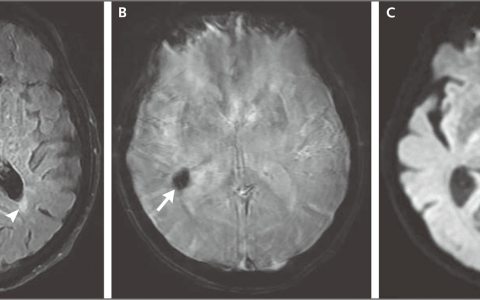

病例6-2023——一名患复发性卒中的68岁男性